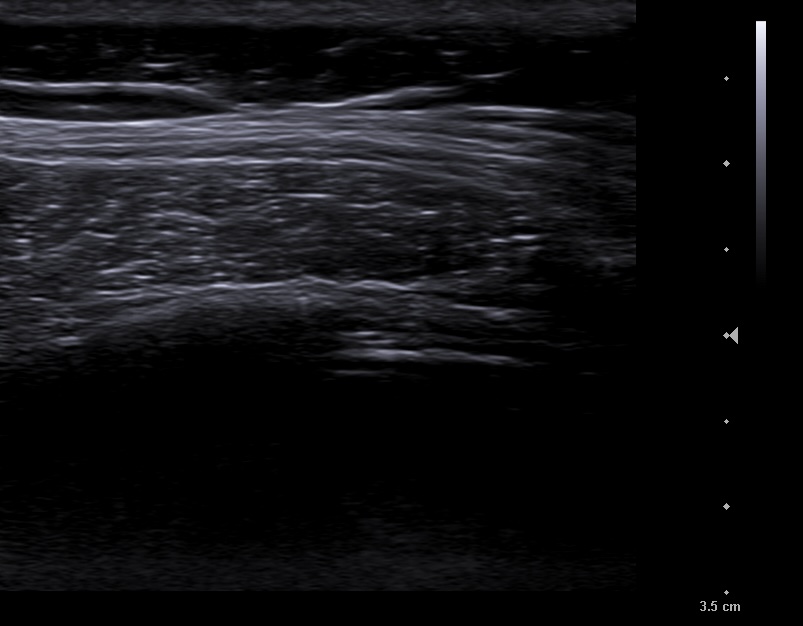

En la ecografía apreciamos en campo derecho un patrón ecográfico tisular, con líneas y puntos hiperecoicos, y algún artefacto en cola de cometa, correspondientes a broncograma aéreo.

Neumonía no complicada en campo pulmonar derecho.